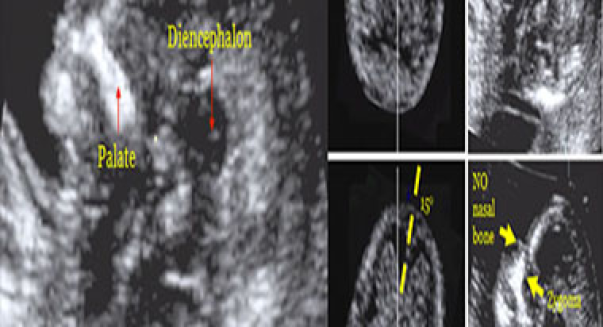

Ecografía genética del primer trimestre (11 a 13.6 semanas)

Permite detectar problemas fetales a través de marcadores ecográficos que sugieren anomalías cromosómicas, congénitas y síndromes genéticos. Se tiene una alta tasa de detección (cercana al 95%) con un bajo porcentaje de falsos positivos (2.5%). Es esencial para mujeres mayores de 35 años.